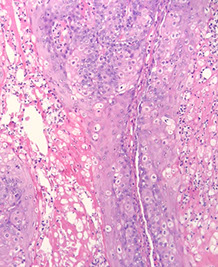

Leukemia cutis

Usually reserved for AML or some other kind of nasty leukemia involving the skin, not for just some mature B-cell neoplasm involving the skin (would just say, eg,  CLL/SLL involving the skin)

- histiocytes and monocytes like to go to the skin, so things like AMML like to go to the skin, and tend to have a more histiocytic appearance and to stain with CD4

- since the cells are more monocytic in the skin, tend to stain less with the markers that they would stain with in the bone marrow, such as CD117

Micro: sheets of malignant cells with reticular dermal collagen intact

If you see this and the clinicians do not know that the patient has leukemia (in the blood) you need to get a PBS immediately and see what is going on in the blood

- it is rare to have leukemia cutis without seeing PB involvement

Ddx: there is a variant of Sweet's syndrome (histiocytoid Sweet's syndrome) with left-shifted myeloid cells that can look like leukemia cutis, which also stains with MPO and may look like leukemic blasts

Leukemia cutis- cells going through collagen bundles because leukemic cells are dyscohesive versus other malignancies

Subtle case of leukemia cutis around hair follicles